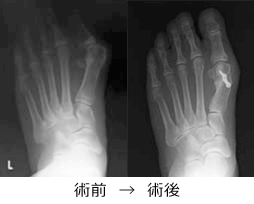

母趾が外側の方に曲がってくる変形です。これによって足指の付け根の関節が飛び出し、しばしば靴にあたり強い痛みをだします。 また、足裏にタコができて、これも痛みの原因となります。

原因として最も大きな要因は、足に合わない靴をはき続けることです。

治療の方法としてあった靴を履くことや運動療法などの保存療法があります。しかし残念ながら、一度曲がった足指が自然にまっすぐに戻ることはありません。徐々に進行します。

我々はレントゲンでの重症度に応じて、手術療法を行っています。手術は中足骨という骨を骨切りして足の形を整える方法です。骨切り部分はスクリューやプレートといった金属で固定します。術後早期から装具を使って歩くことが可能な手術になります。外反母趾でお困りでしたらご相談ください。